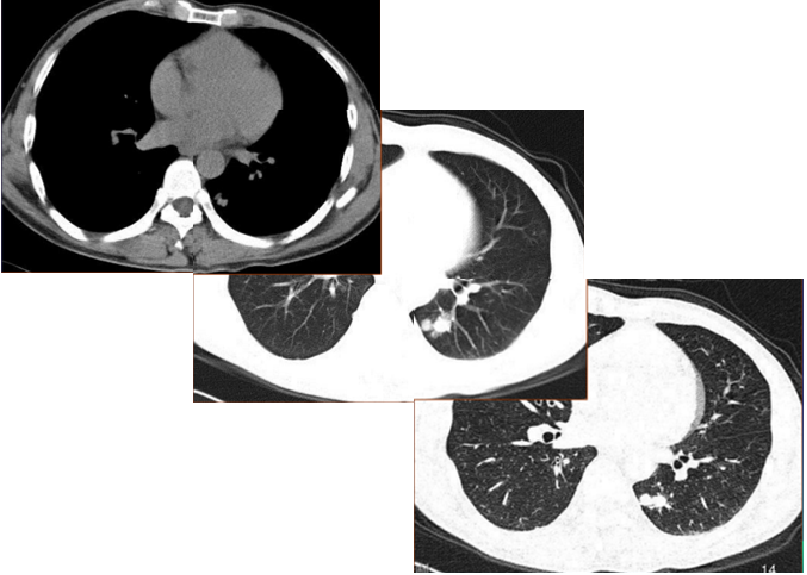

一周后她又来到我中心,要求提前复查,复查薄层 CT,病灶内部出现小空洞,体积较前略缩小,原边缘磨玻璃渗出吸收消失。我中心给出诊断结论:为肺隐球菌感染。她本人以及我中心都是最幸福的时刻,因为又一位「患者」摆脱了「肿瘤」的困扰。

HRCT 见血管及支气管贴边征,未见明显血管集束征、毛刺及支气管截断征。

随访:临床治疗一周后复查薄层 CT,病灶内部出现小空洞,体积较前略缩小,原边缘磨玻璃渗出吸收消失。